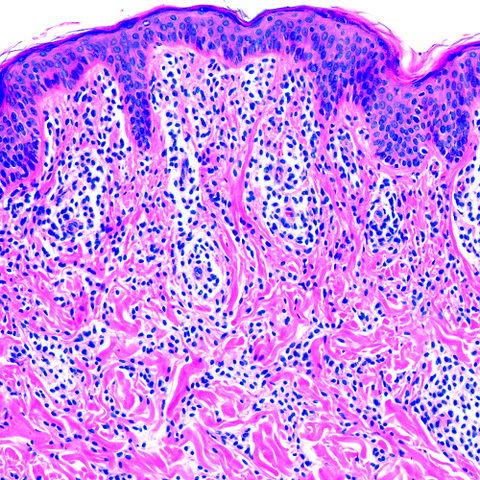

Microscopic (histologic) description

- Within the macules and plaque, mast cells are predominantly in papillary dermis

- Mast cells are round or spindle shaped with abundant eosinophilic cytoplasm, distinct cytoplasmic boundaries, large pale nuclei

- Eosinophils are often present

- Also edema of papillary dermis, subepidermal vesiculation

- In telangiectasia macularis eruptive perstans, features may be subtle, with increased mast cells around dilated superficial capillaries, basal cell hyperpigmentation of overlying epidermis, superficial lymphohistiocytic infiltrate

Microscopic (histologic) images